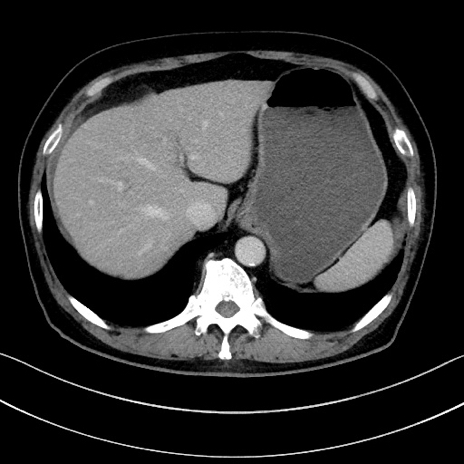

冠状断像

【症例】70歳代男性

【主訴】腹痛

【現病歴】今朝から腹痛あり。全体的に痛い。特に左上の方。排ガスが今日はない。冷や汗が出る。

【既往歴】直腸癌術後

【身体所見】左側腹部〜上腹部に圧痛あり。腹膜刺激症状明らかなではない。軽度反跳痛。左下腹部に術後瘢痕あり。

【データ】WBC 7700、CRP 0.02